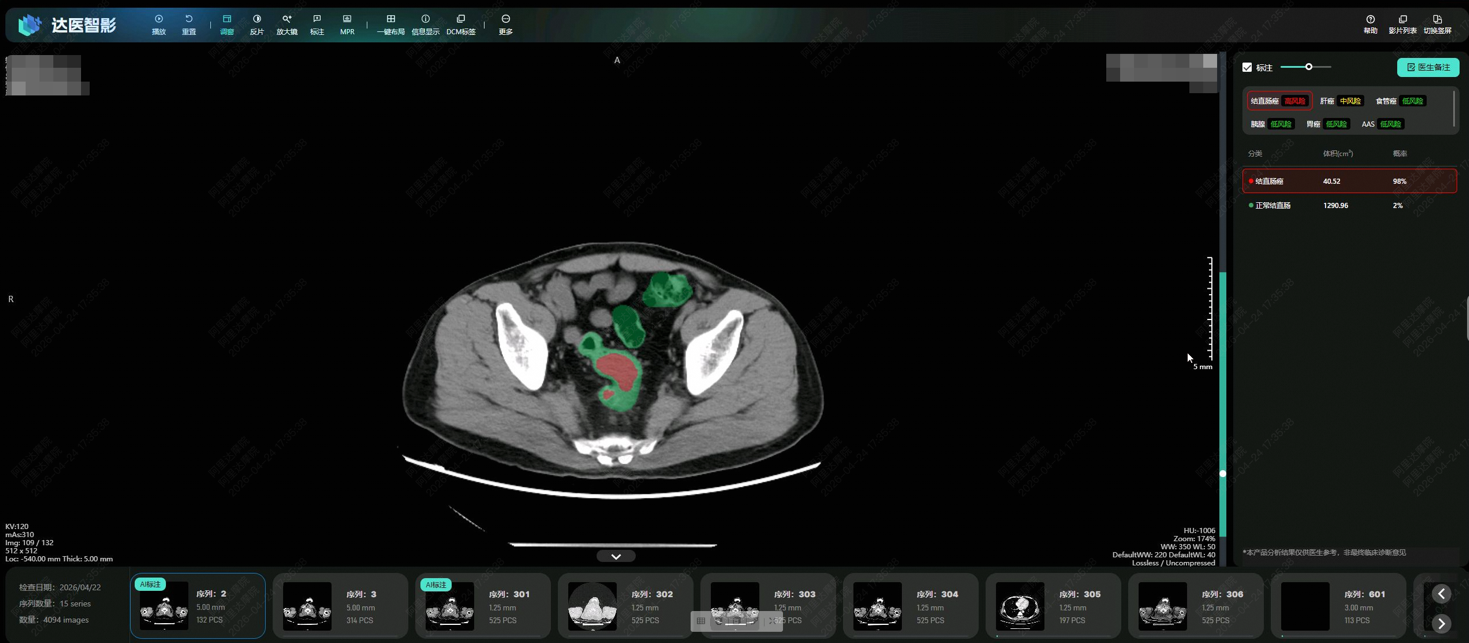

DAMO COCA模型自动识别结直肠癌风险

据悉,达摩院创新性地提出了用“平扫CT+AI”实现肠癌“机会性筛查”。平扫CT在国内广泛用于健康体检、创伤评估、腹痛排查,每年产生上亿份影像,如能从中检测肠癌病灶,就不用增加额外检查,顺带排查肠癌风险。然而,拍平扫CT时患者不做肠道准备,肠道内容物严重干扰平扫CT影像,医生判读难度极大。

为此,达摩院发挥在“平扫CT+AI”方面的多年技术积累,采用“先定位、后诊断”的两阶段深度学习架构和混合监督学习策略,更针对小于3厘米的早期肿瘤专门训练,使得AI模型能精细分割形态复杂的肠道部位并克服内容物干扰,日韩a毛片免费观看中日韩视频在线观看检测可疑病灶。

研究团队将AI模型部署在医院开展了两轮真实世界试验,共回顾了27433人的平扫CT影像,从中发现5例被遗漏的肠癌患者。其中一名患者曾连续两年拍摄平扫CT,均未检出肠癌,直到第三年通过肠镜确诊,此时肿瘤已发展增大。这意味着,AI模型可帮助类似情况的患者通过平扫CT更早发现异常,及时治疗。

“肠道病灶在平扫CT影像上极易被遗漏,而DAMO COCA这样的AI工具能有效帮助医生解决这一痛点,赋能临床诊疗,也帮助更多患者在无需肠道准备的情况下机会性发现健康隐患”,广东省人民医院放射科主任刘再毅表示,“未来,需要把AI模型部署到更多地区和机构,通过大规模的前瞻性研究,进一步获得高质量循证证据。”